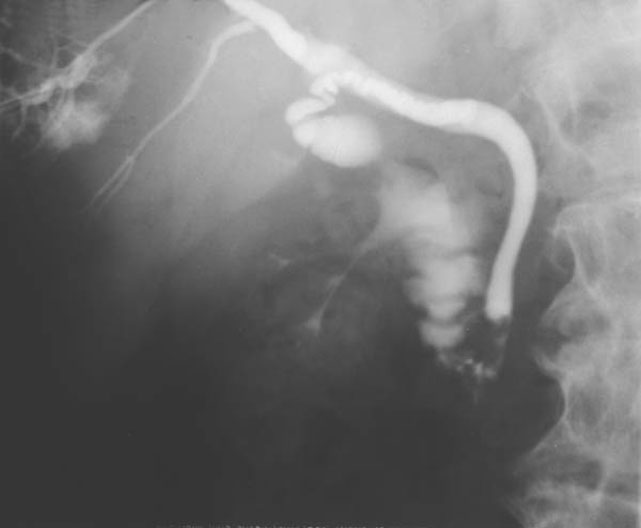

Cholangiogram

1. Gall Bladder

2. Duodenum

3. Intrahepatic Duct

4. Cystic Duct

5. Common Bile Duct